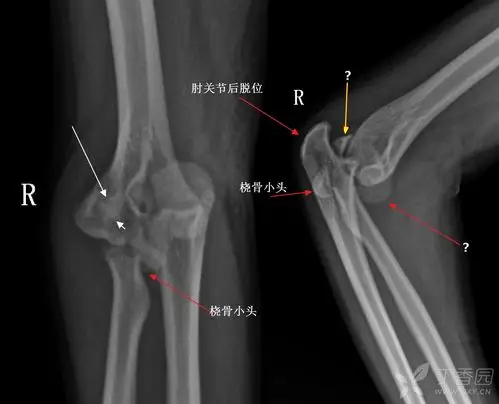

肘关节骨折伴脱位